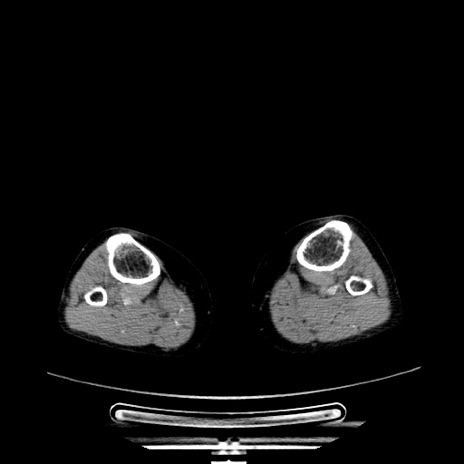

症例5(横断像)

【症例】70歳代女性

【主訴】お腹が張る

【現病歴】1週間くらい前から腹部膨満の自覚あり。昨日夜から増悪したため、本日救急外来受診。

【身体所見】意識清明、BT 36.5℃、BP 165/106mmHg、HR 80bpm、SpO2 98%、腹部:膨満、軟、自発痛・圧痛なし、触診にて不快感あり、腸蠕動音:減弱

【データ】WBC 12600、CRP 1.04